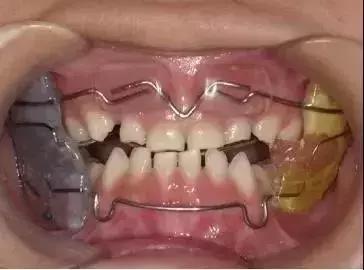

03、上颌颌垫活动矫治器

简单点说,就是喊你把这个上颌颌垫活动矫治器戴到起。

04、下颌斜面导板矫治器

还是简单点说,喊你把这个下颌斜面导板矫治器戴到起。你是不是要问“那跟上面那个有啥不同嘛”?回答:因为娃娃的患病情况不同嘛!

06、功能调节器(简称FR-Ⅲ)

看起来是有点不美观哈,但总比一直“地包天”不美观好撒!